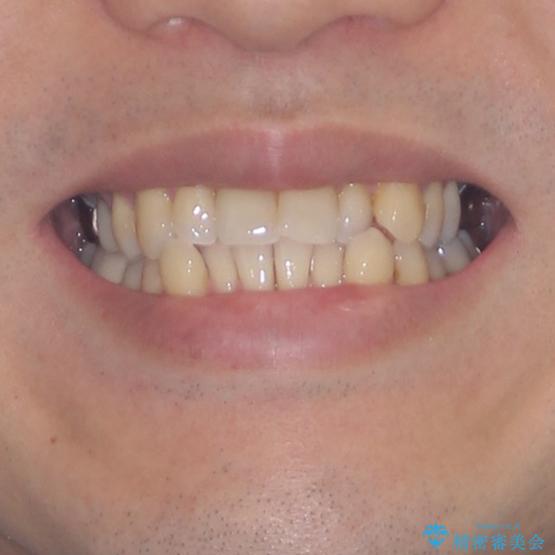

受け口傾向の咬み合わせ 前歯のデコボコをワイヤー矯正で素早く改善

- 前歯の見た目を気にして来院された患者様です。

ワイヤー矯正でもマウスピース矯正でも対応可能とお伝えし、非常に悩まれていましたが、2年後に転勤の可能性が高いとのことで、治療終了までの期間を想定しやすいワイヤー矯正にて治療を行うこととしました。

この患者様もクロスバイトはあっという間に改善され、1年強で速やかに治療を終えることができました。